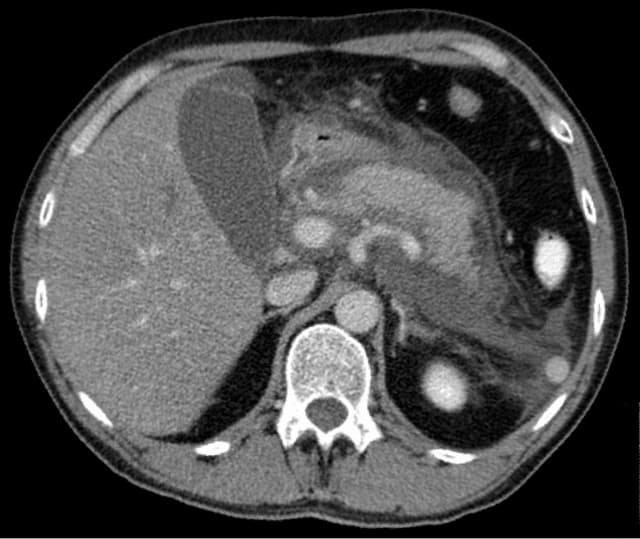

https://en.wikipedia.org/wiki/Acute_pancreatitis